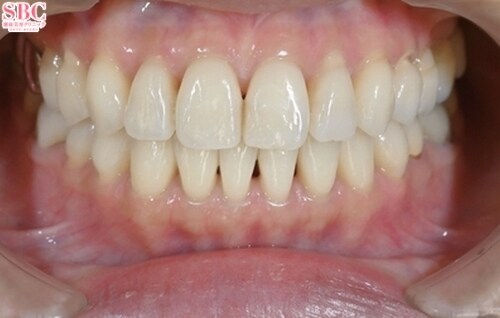

施術前

「前歯の捻じれ、歯の重なりがきになる」とのことでインビザラインモデレートにて治療したお写真になります★約7か月ほどできれいに並びました!マウスピース矯正は一日20時間以上マウスピースを使用し1週間?10日位の交換で進めていきます。スペースが足りない場合はIPR(歯と歯の間を削ってスペースを作る処置)やゴムかけが必要になる場合がございます。どのプランが適切かカウンセリング時にご説明させていただきます★ご興味ある方は是非カウンセリングにいらしてくださいませ。お待ちしております!

「前歯の捻じれ、歯の重なりがきになる」とのことでインビザラインモデレートにて治療したお写真になります★

約7か月ほどできれいに並びました!

マウスピース矯正は一日20時間以上マウスピースを使用し1週間?10日位の交換で進めていきます。

スペースが足りない場合はIPR(歯と歯の間を削ってスペースを作る処置)やゴムかけが必要になる場合がございます。

どのプランが適切かカウンセリング時にご説明させていただきます★